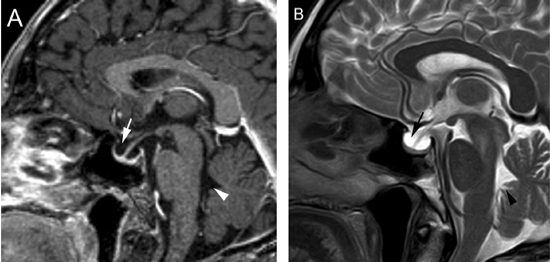

Figura 9A y B. Cortes sagitales, secuencias T1wl con Gadolinio y T2w, muestran la hipófisis en la porción inferior de la fosa pituitaria, lo que es secundario a una herniación de la cisterna supraselar (flecha). Obsérvese que el tallo pituitario esta también descendido. La secuencia T2w permite confirmar que la señal del líquido en la fosa pituitaria es similar al LCR del IV ventrículo (punta de flecha). Tumores pituitarios